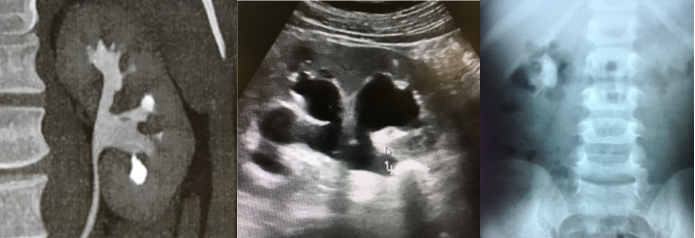

Figura 1 – três indicações clássicas para mini percutânea – infundíbulo estreito em cálculo calicial inferior com ângulo desfavorável, cálculo volumoso em ureter superior, cálculo em criança.

![]()